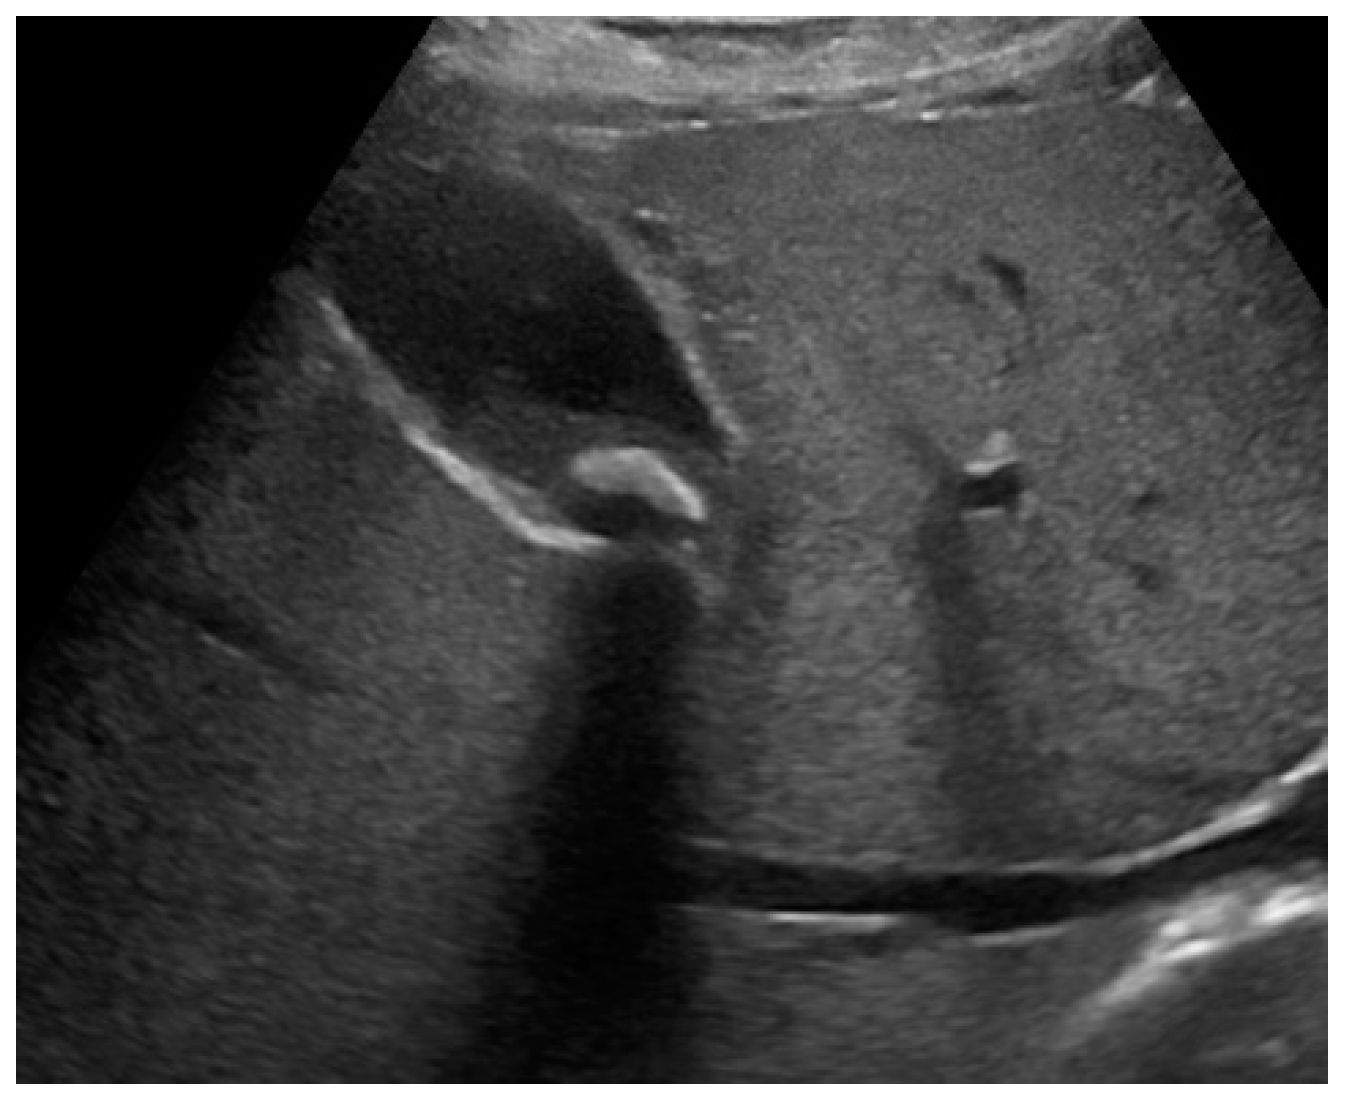

Mirizzi syndrome is generally suspected in course of abdominal US, which shows dilatation of the biliary system above the level of the gallbladder neck or cystic duct, in presence of one or more stones. Distally to the stenosis, the common bile duct maintains a normal caliber. [32,44,80] Sonographic findings may include gallbladder hydrops, contracted atrophic gallbladder or, in case of concomitant AC, gallbladder wall thickening. US sensitivity is reported to be up to 50%, and in a single study even 77%. [80,81,82] The presence of malignancy must be ruled out before therapeutic decision.